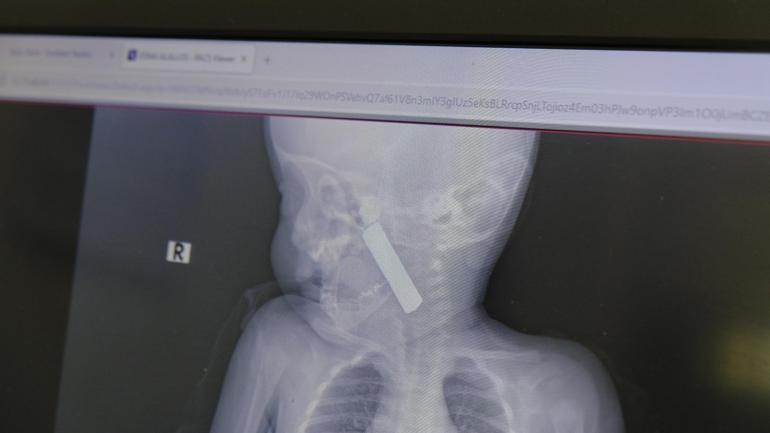

Edinilen bilgiye göre, kusma şikayeti ile ailesi tarafından Karaman Eğitim ve Araştırma Hastanesi acil servisine getirilen 6 aylık E.A. isimli kız bebeğin, yapılan muayene ve tetkiklerde boğazında kumanda pili kaçtığı tespit edildi.

Yaşanan olayla ilgili bilgi veren Doç. Dr. Mehmet Uysal, "Acil polikliniğimize kusma şikayeti ile 6 aylık bir kız bebek getirilmiş ve bize haber verildi. Biz de vakit kaybetmeden geldik, hastamızı gördük. Yapılan tetkikler sonucunda, ağız tabanına oturan ve yemek borusunun birinci darlığına kadar uzanan, kumanda pili dediğimiz bir pille karşılaştık. Filmde ve muayenede bunu gördük. Hastayı ilk gördüğümüzde bayağı siyanotik durumda, solunum sıkıntılıydı ve oksijen satürasyonu 90 civarındaydı. Böyle olunca bir an önce beklemeden hızlı bir şekilde ameliyathaneye götürdük. Orada ameliyathanedeki anestezi uzmanlarımız ve personel bize yardımcı oldu, hasta hızlı bir şekilde entübe edildi. Ondan sonra da laringoskop ve magill forseps dediğimiz malzemelerimizle bu yabancı cismi çıkarmış olduk. Bir an evvel müdahale ettik, iyi ki müdahale ettik, orada ağız tabanında, özellikle ön kısmında hasar oluşmuştu. Müdahale sonrasında da hastanın solunum problemleri bir süre devam etti, bu yüzden 24 saat takip ettik. Herhangi bir problem oluşmayınca 24 saat sonra kontrole gelmek üzere hastayı taburcu ettik" diye konuştu.